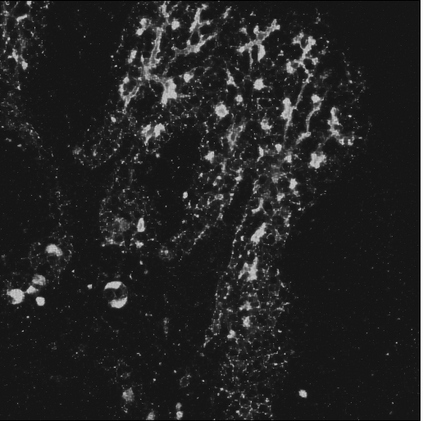

Motivated by the challenging segmentation task of pancreatic tubular networks, this paper tackles two commonly encountered problems in biomedical imaging: Topological consistency of the segmentation, and expensive or difficult annotation. Our contributions are the following: a) We propose a topological score which measures both topological and geometric consistency between the predicted and ground truth segmentations, applied to model selection and validation. b) We provide a full deep-learning methodology for this difficult noisy task on time-series image data. In our method, we first use a semisupervised U-net architecture, applicable to generic segmentation tasks, which jointly trains an autoencoder and a segmentation network. We then use tracking of loops over time to further improve the predicted topology. This semi-supervised approach allows us to utilize unannotated data to learn feature representations that generalize to test data with high variability, in spite of our annotated training data having very limited variation. Our contributions are validated on a challenging segmentation task, locating tubular structures in the fetal pancreas from noisy live imaging confocal microscopy. We show that our semi-supervised model outperforms not only fully supervised and pre-trained models but also an approach which takes topological consistency into account during training. Further, our approach achieves a mean loop score of 0.808 for detecting loops in the fetal pancreas, compared to a U-net trained with clDice with mean loop score 0.762.